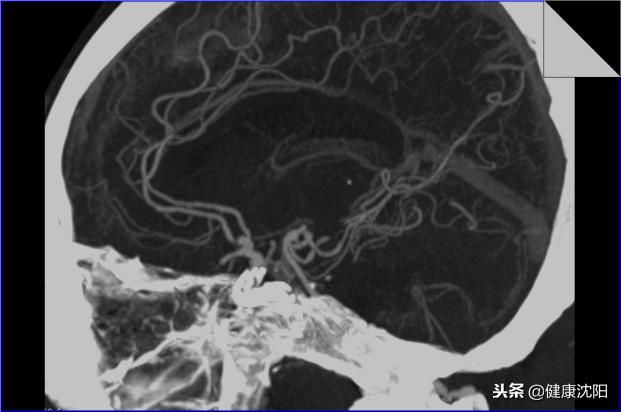

显示颅内血管的解剖及病变

显示椎-基底动脉-大脑后动脉系统血管的平面解剖

清晰显示大脑前动脉的平面解剖关系